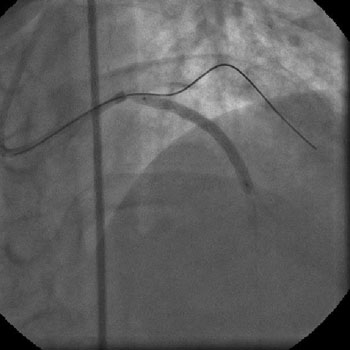

Angiography

1) RCA: Discrete severe mid stenosis (Figure 1)